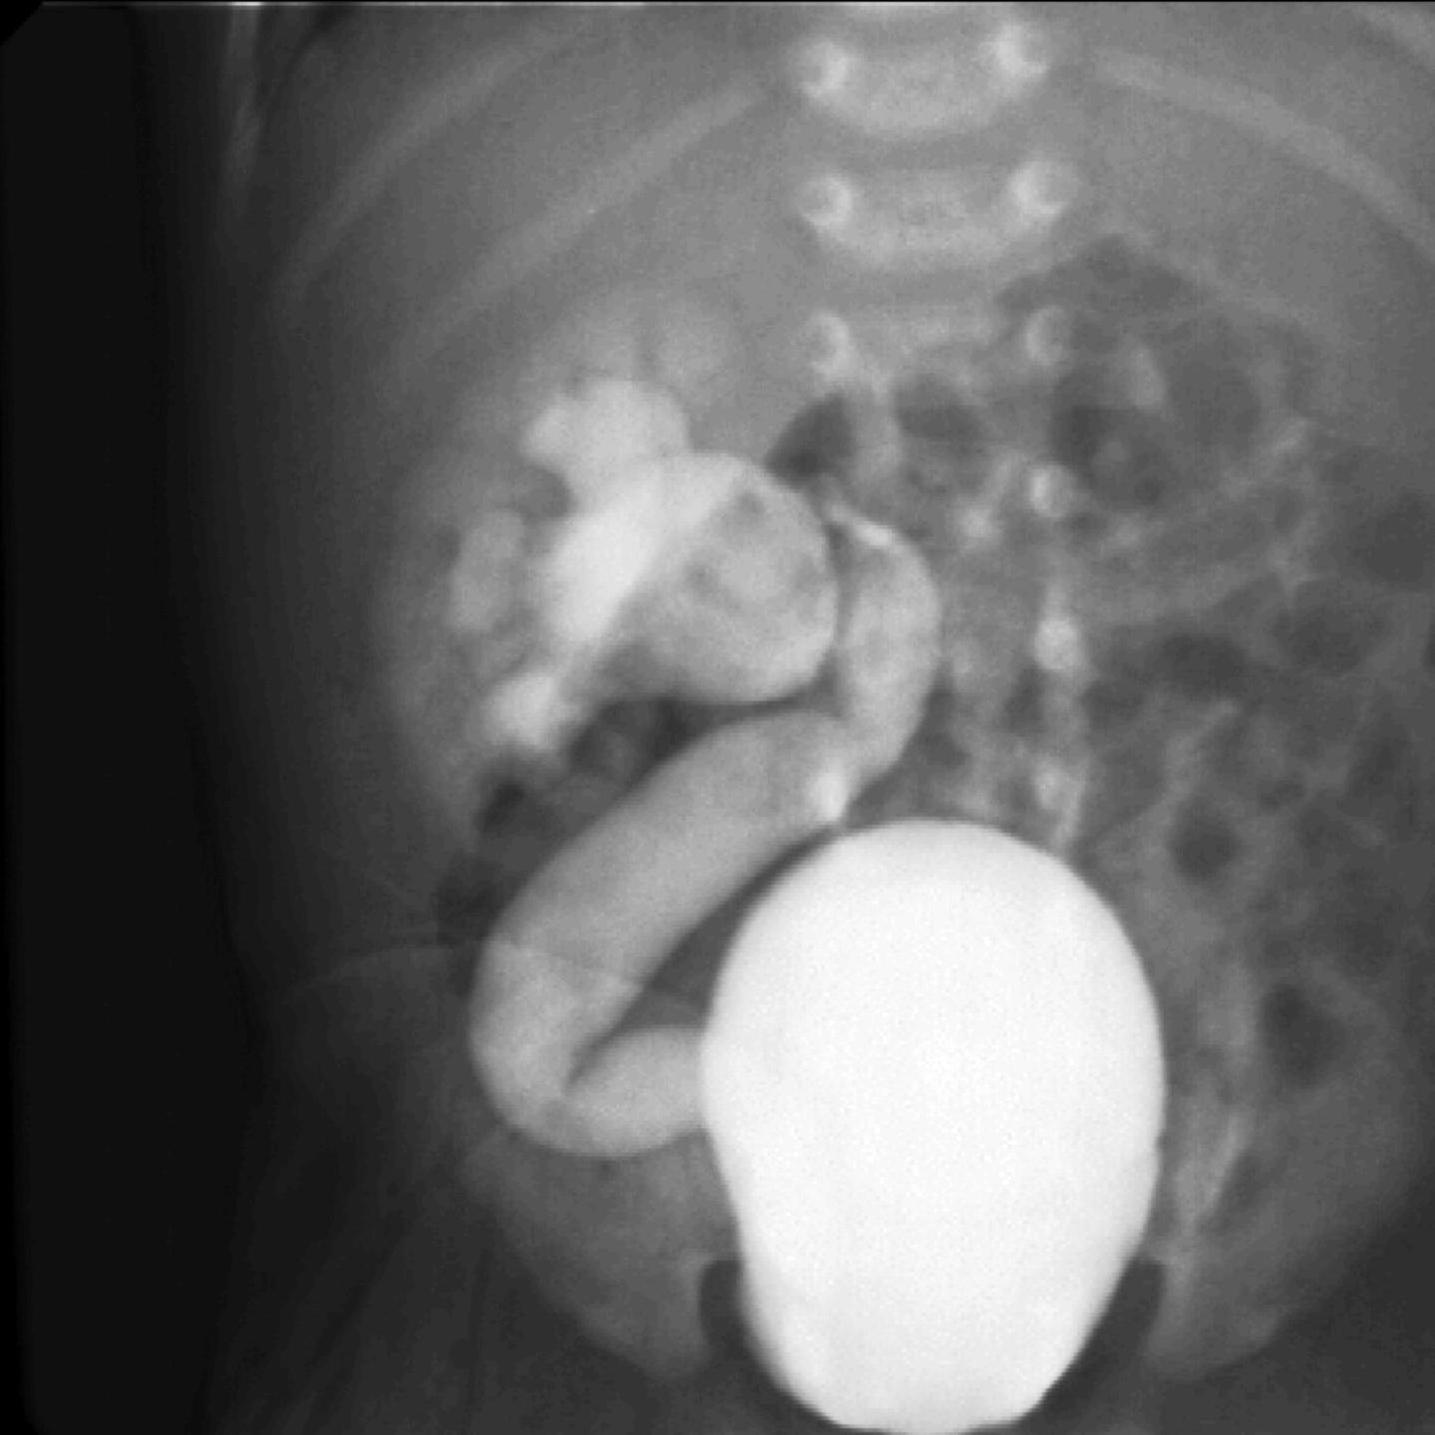

Malrotation-volvulus. During the normal development of the intestinal tract, the intestinal loops make three 90 degree clock-wise rotations around the mesenteric superior artery (MSA.) If this rotation only partially occurs during the embryonic development the intestines remain in a non-rotational or malrotational position, the mesenteric root will be shorter and the cecum will be weakly attached. This anatomic positioning can be symptom free throughout a lifetime, but it predisposes for volvulus. Volvulus can occur at any age, but it is most frequent in the first months of life, when it abruptly occurs with acute bilious vomiting. In this state the intestines around the mesenteric root twist, end up in a complete obstruction that can lead to a rapid death of the intestines. Ultrasonography can depict the mesenteric superior vein (MSV) coiled up around the MSA, so called “whirlpool”-sign.

During X-ray examination the contrast material does not progress to the jejunal loops or it shows a “corkscrew” sign on the right side of the vertebrae as it piles up in the twisted intestinal loops.

Image

15. Contrast material empties the stomach slowly, small intestines are found on the right side of the abdomen. Malrotation-volvulus.